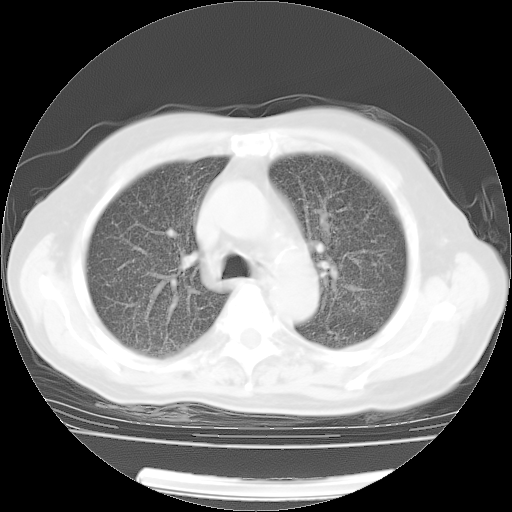

4月14日肺部CT

肺部CT平扫未见异常。